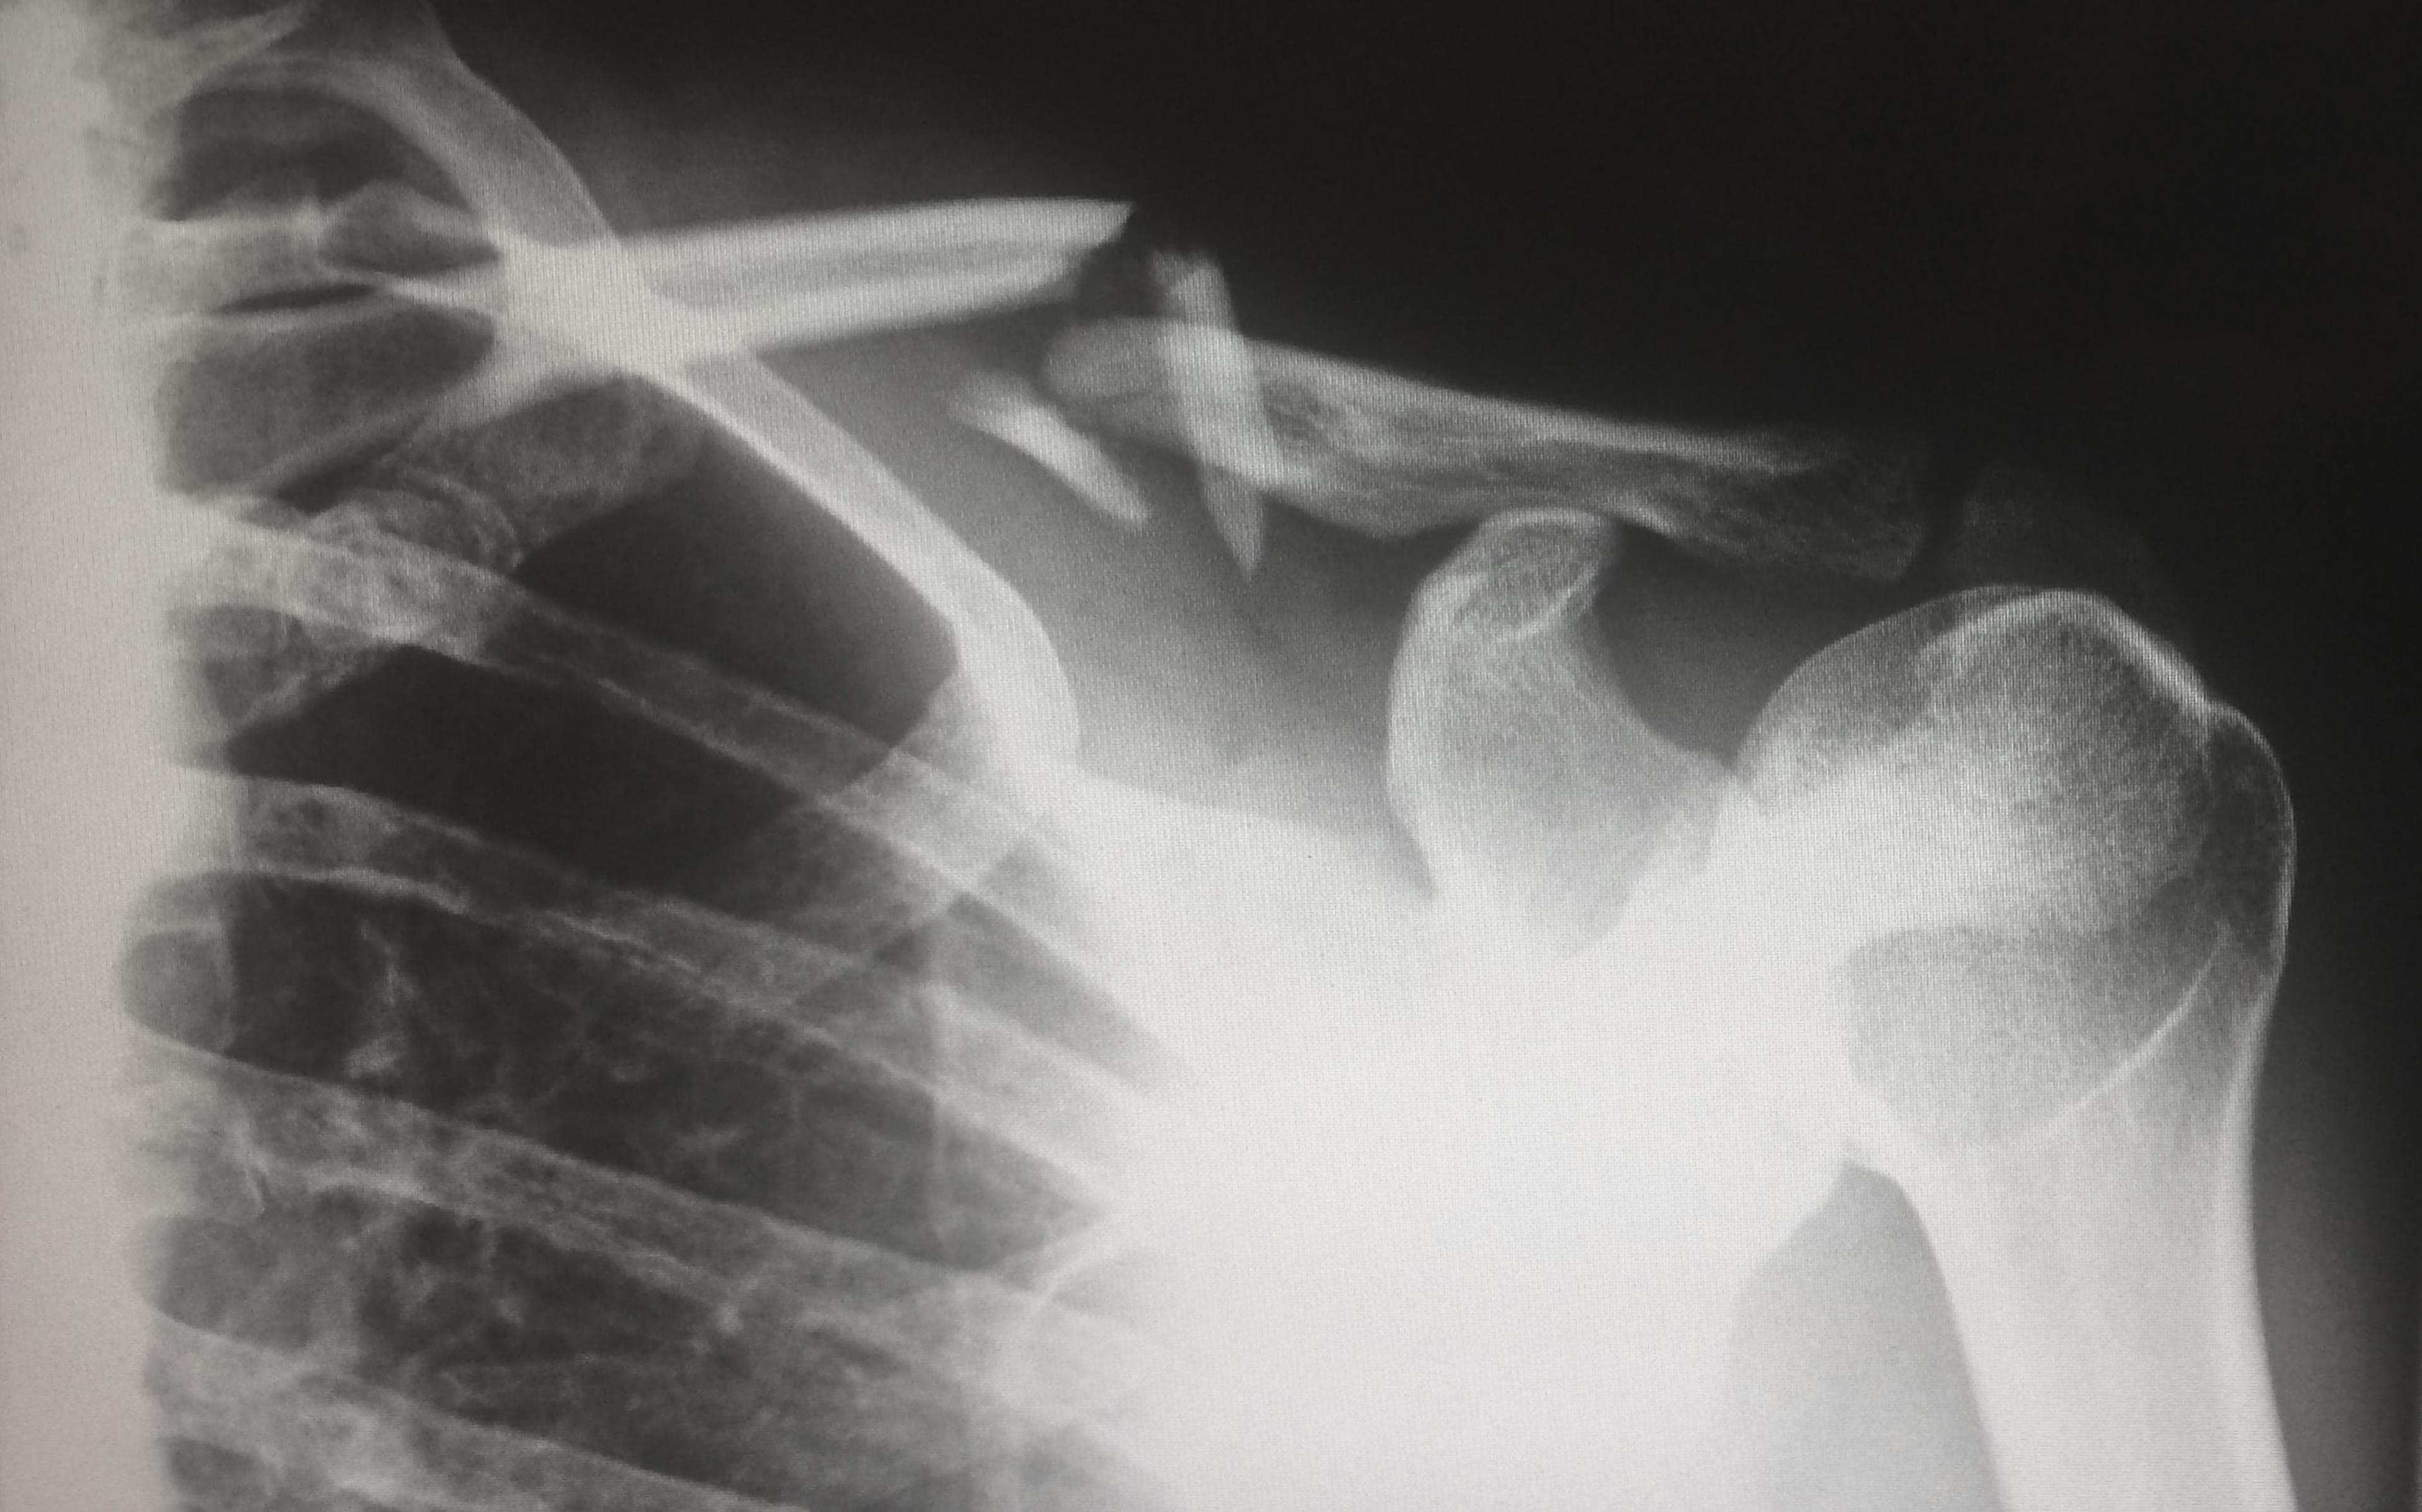

Common symptoms of acromial impingement include shoulder pain, especially during overhead movements, weakness, limited range of motion, and discomfort at rest. Diagnosis typically involves a comprehensive evaluation of the individual’s medical history, physical examination, and imaging techniques such as X-rays, MRI, or ultrasound to assess the shoulder structures and identify any abnormalities.